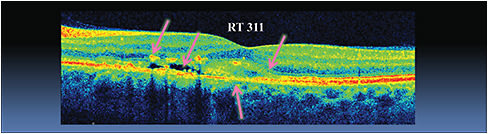

Dilated fundus exam shows pigmentary changes and drusen OU (Figure 1a and 1b). SDOCT OS shows intraretinal fluid, pigment migration into the intraretinal space, disruption of the retinal pigment epithelium (RPE) and a hyper-reflective lesion above the RPE (Figure 2).

For example, a patient being followed for AMD who shows signs of early conversion to wet AMD, such as intraretinal fluid, subretinal fluid or an anomalous hyper-reflective area within the vicinity of the RPE (Figure 2) on SDOCT, should be evaluated by a retinal specialist within 72 hours.